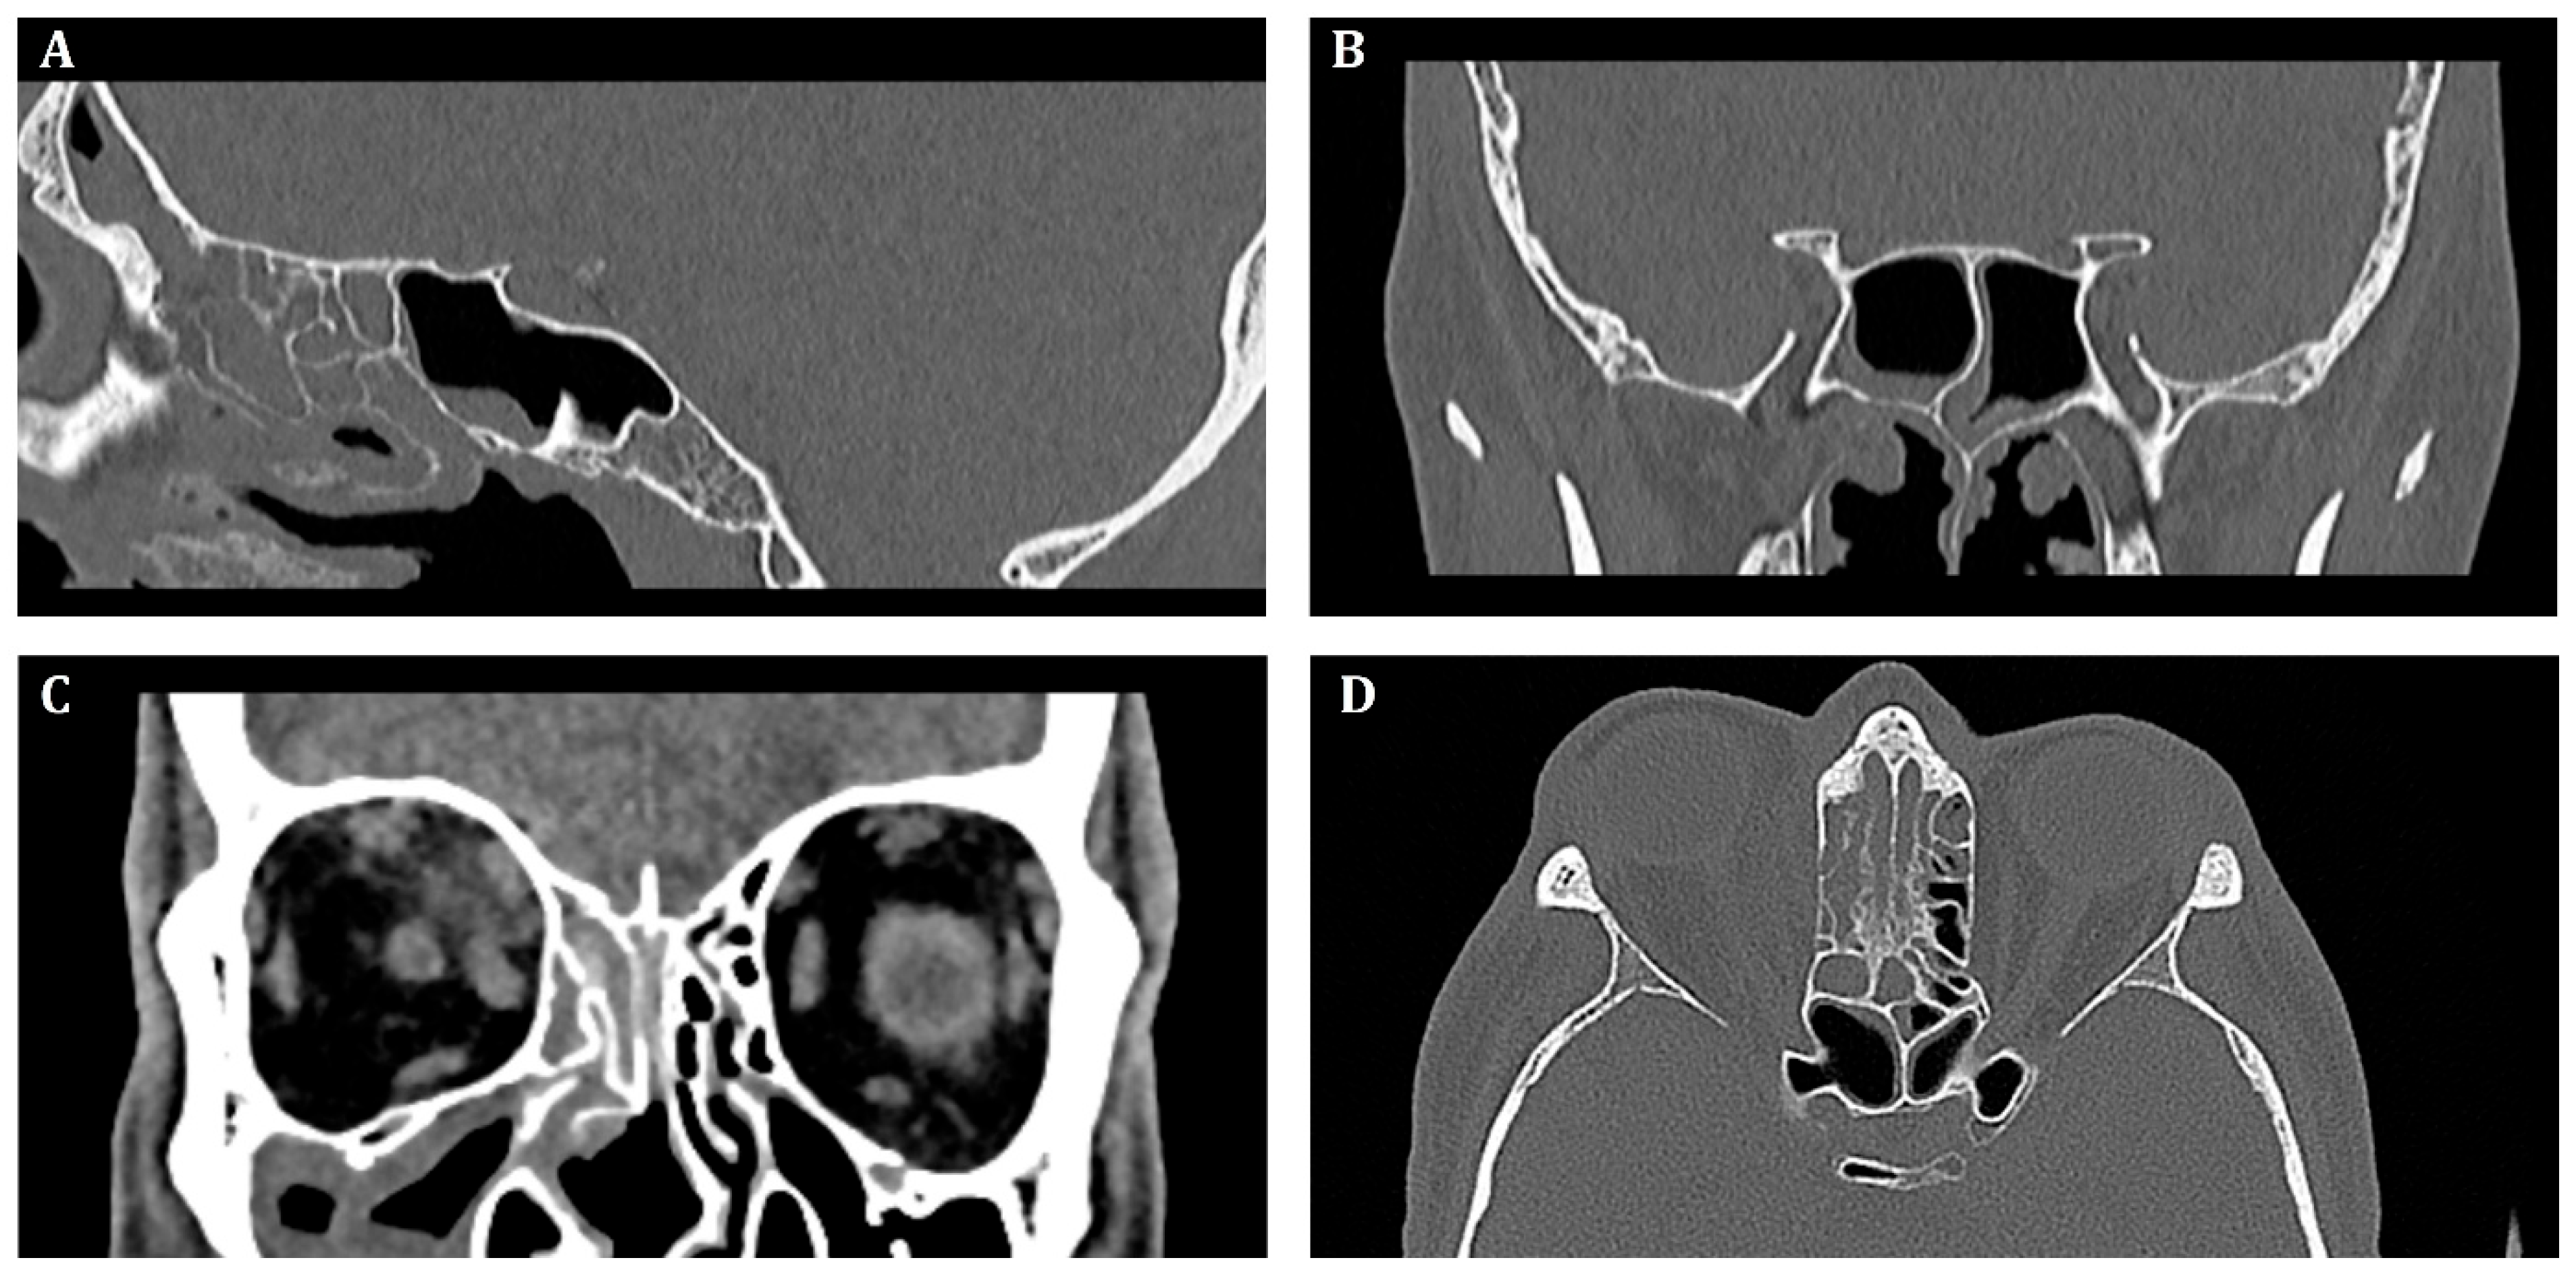

At the patient’s initial presentation at the Otolaryngology Department of the secondary hospital, the magnetic resonance imaging (MRI) of orbits revealed infiltration of the right frontal, ethmoid and maxillary sinuses, extension into the right orbit’s soft tissue and extraocular muscles with optic nerve invasion (Figure 1). The ophthalmological examination revealed central retinal artery occlusion. The treatment with ceftriaxone, vancomycin, fluconazole, mannitol and methylprednisolone was initiated. Due to clinical suspicion of mucormycosis, the patient was transferred to the University Hospital in Cracow.

Figure 1. Initial pre-operative magnetic resonance imaging. T2-weighted MRI scans of the orbits. (A)—sagittal, (B)—frontal, (C)—transverse planes. Visible infiltration of extraocular muscles and optic nerve. Inflammatory opacifications in ethmoid cells and maxillary sinus, extending into the orbital adipose tissue and extraocular muscles, causing osseous destruction of ethmoid cells.